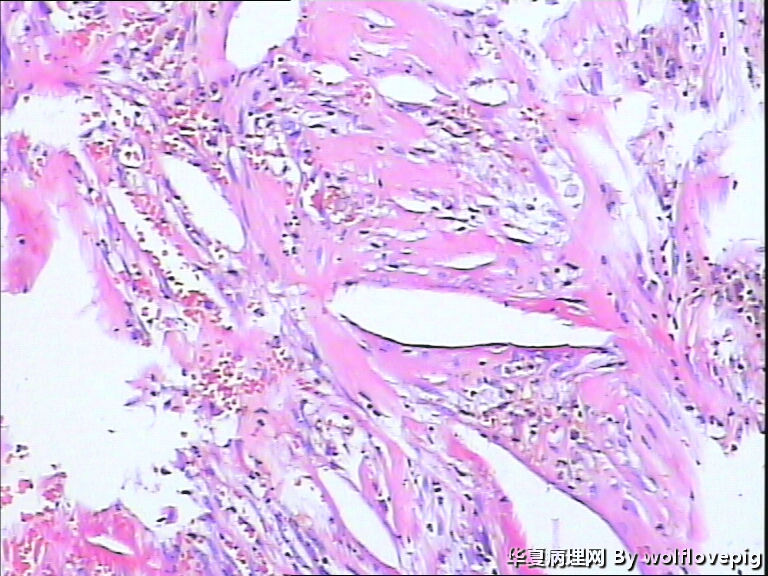

男,70y,左腰痛一年,反复血尿1月,坐肾区轻叩痛。

• 求助!肾脏包块!图4

图4

大体图片有些让人担心。镜下图片更倾向是良性病变。主要为对坏死组织的反应。

图片质量非常不好,显微镜下的图片几乎没法观察, 看大体标本还是不能除外肿瘤性病变,能不能采一些高质量的图片?

炎症性病变